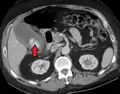

استخدام الموجات الفوق صوتية هو أهم خطوة من خطوات التصوير الإشعاعي ومن ثم التصوير المقطعي.

Acute cholecystitis with gallbladder wall thickening, a large gallstone, and a large gallbladder